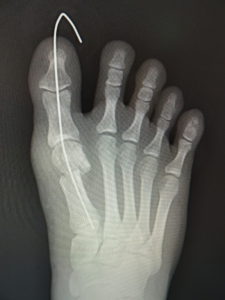

手術前 手術後4年

最近では、原則として固定ワイヤーは経皮的の一本のみとし、ワイヤーの先端は皮膚の外に出ているので、抜く時(術後3週間目)の患者さんの負担はほぼありません。こうすることによるデメリットはなく、むしろ術後成績は良くなっています。

(図6)

手術前 手術後

(図7)

真田理事長による手術の様子。外反母趾|症例 (左から 手術前、手術後、ワイヤ抜去後)